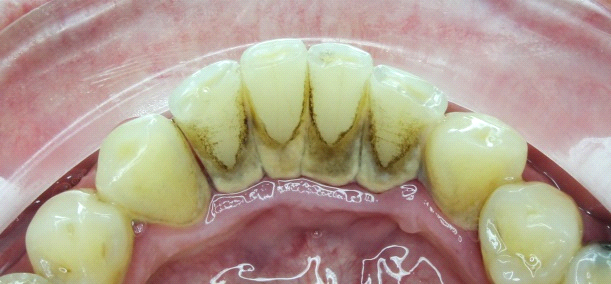

A dentálhigiénikus ezután hozzákezd a fogai tisztításához. Ultrahang segítségével eltávolítja a fogkövet, amely a fogakon megtapadt lepedék mineralizációja révén alakul ki, s amely idővel fogszuvasodást okoz. Az egész folyamat alapja, hogy az ultrahang megszünteti a fogkő tapadását, így az leesik. Mechanikus eltávolítás esetén kis kaparókat használ.

A lepedék és az elszíneződések (kávé, cigaretta, étel...) eltávolítására a szakember keféket, speciális fogkrémeket és “air flow” polírozást alkalmaz. Ez az eljárás szépen kifényesíti és megtisztítja a fogakat egy igen finom szemcsés anyag, víz és levegő keverékével.